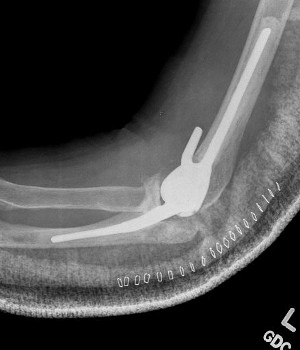

Total Elbow Replacement

A surgical procedure performed to replace worn joint surfaces in the elbow, usually due to severe arthritis. An incision is made to access the joint and the worn surfaces are removed. Artificial components with stems are then cemented into the canals of the ulna and humerus. The components fit together and create a metal and plastic hinge at the joint. When all of the components are in place the elbow is checked to ensure appropriate range of motion, alignment, and stability.

An incision is made at the back of the elbow and the worn surfaces are removed. Replacement stems are placed into both the ulna and the humerus and secured with cement.

What are the implants made of in a total elbow arthroplasty?